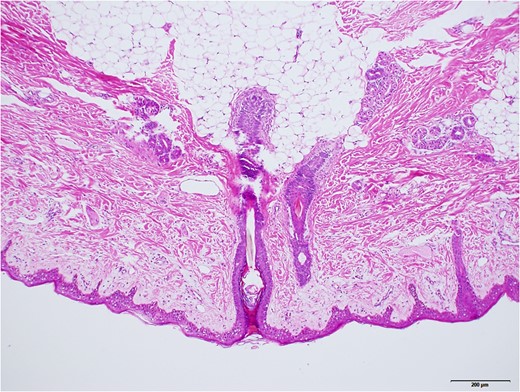

Grossly, protruded part of the mass was covered with sparsely haired skin. Sub-conjunctival part was covered with thin capsule with vasculatures (Fig. 5). Histopathologically, most part of the mass was composed of mature adipose tissue, lobuled by fibrous septum with vasculatures (Fig. 6). Outer surface was covered with squamous epidermis with normal rete ridge. In dermal layer, appendages, including hair follicles, sebaceous glands and sweat glands were seen (Fig. 7). Dense fibrous tissue was seen surrounded by the adipose tissue. This was assumed to be the link of palpebral tarsal plate (Fig. 8). No lacrimal grand tissue was identified.

Higher magnified surface area, taken with ×10 objective lens. Black bar represents 200 μm. Mature hair follicles, sebaceous glands, and sweat glands were observed.